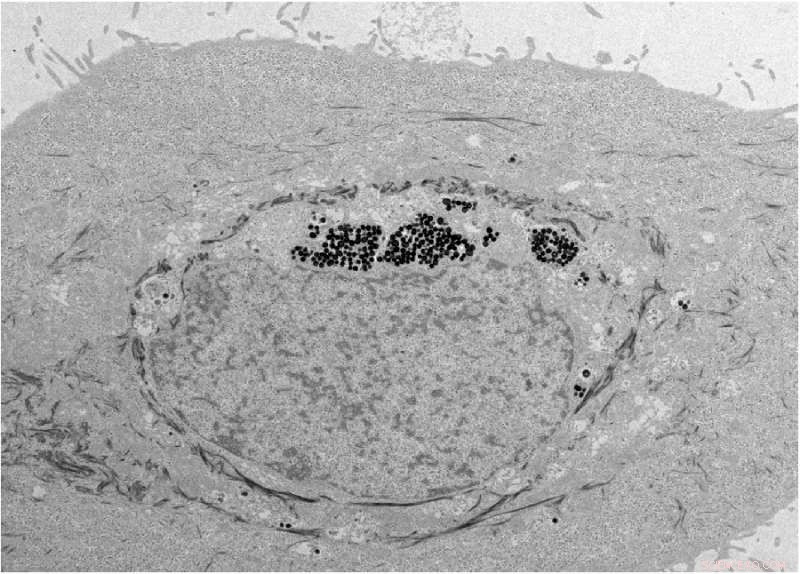

Scanning electron microscope image of the synthetic melanin-like nanoparticles, which protected skin cells from DNA damage. Credit: Yuran Huang and Ying Jones, UC San Diego

The scientists found that the synthetic nanoparticles were taken up in tissue culture by keratinocytes, the predominant cell type found in the epidermis, the outer layer of skin. Credit: Yuran Huang and Ying Jones/UC San Diego

"We hypothesized that synthetic melanin-like nanoparticles would mimic naturally occurring melanosomes and be taken up by keratinocytes, the predominant cell type found in the epidermis, the outer layer of skin," said Gianneschi.

In healthy humans, melanin is delivered to keratinocytes in the skin after being excreted as melanosomes from melanocytes.The UC San Diego scientists prepared melanin-like nanoparticles through the spontaneous oxidation of dopamine—developing biocompatible, synthetic analogues of naturally occurring melanosomes. Then they studied their update, transport, distribution and ultraviolet radiation-protective capabilities in human keratinocytes in tissue culture.

The researchers found that these synthetic nanoparticles were not only taken up and distributed normally, like natural melanosomes, within the keratinocytes, they protected the skin cells from DNA damage due to ultraviolet radiation.